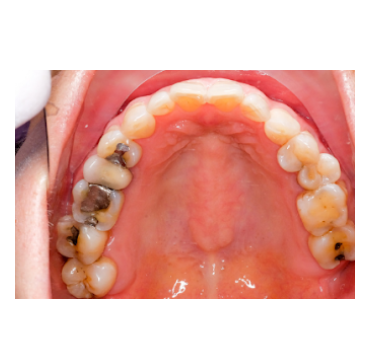

Dental Fillings

At GUGU Dental Clinics in Saibaba Colony, Coimbatore, we use the modern dental filling materials to refurbish cavities and damaged teeth. The filling process is done under local anesthesia and is completely painless. And then our Dentist will organize the space for the filling by cleaning the cavity of particle.